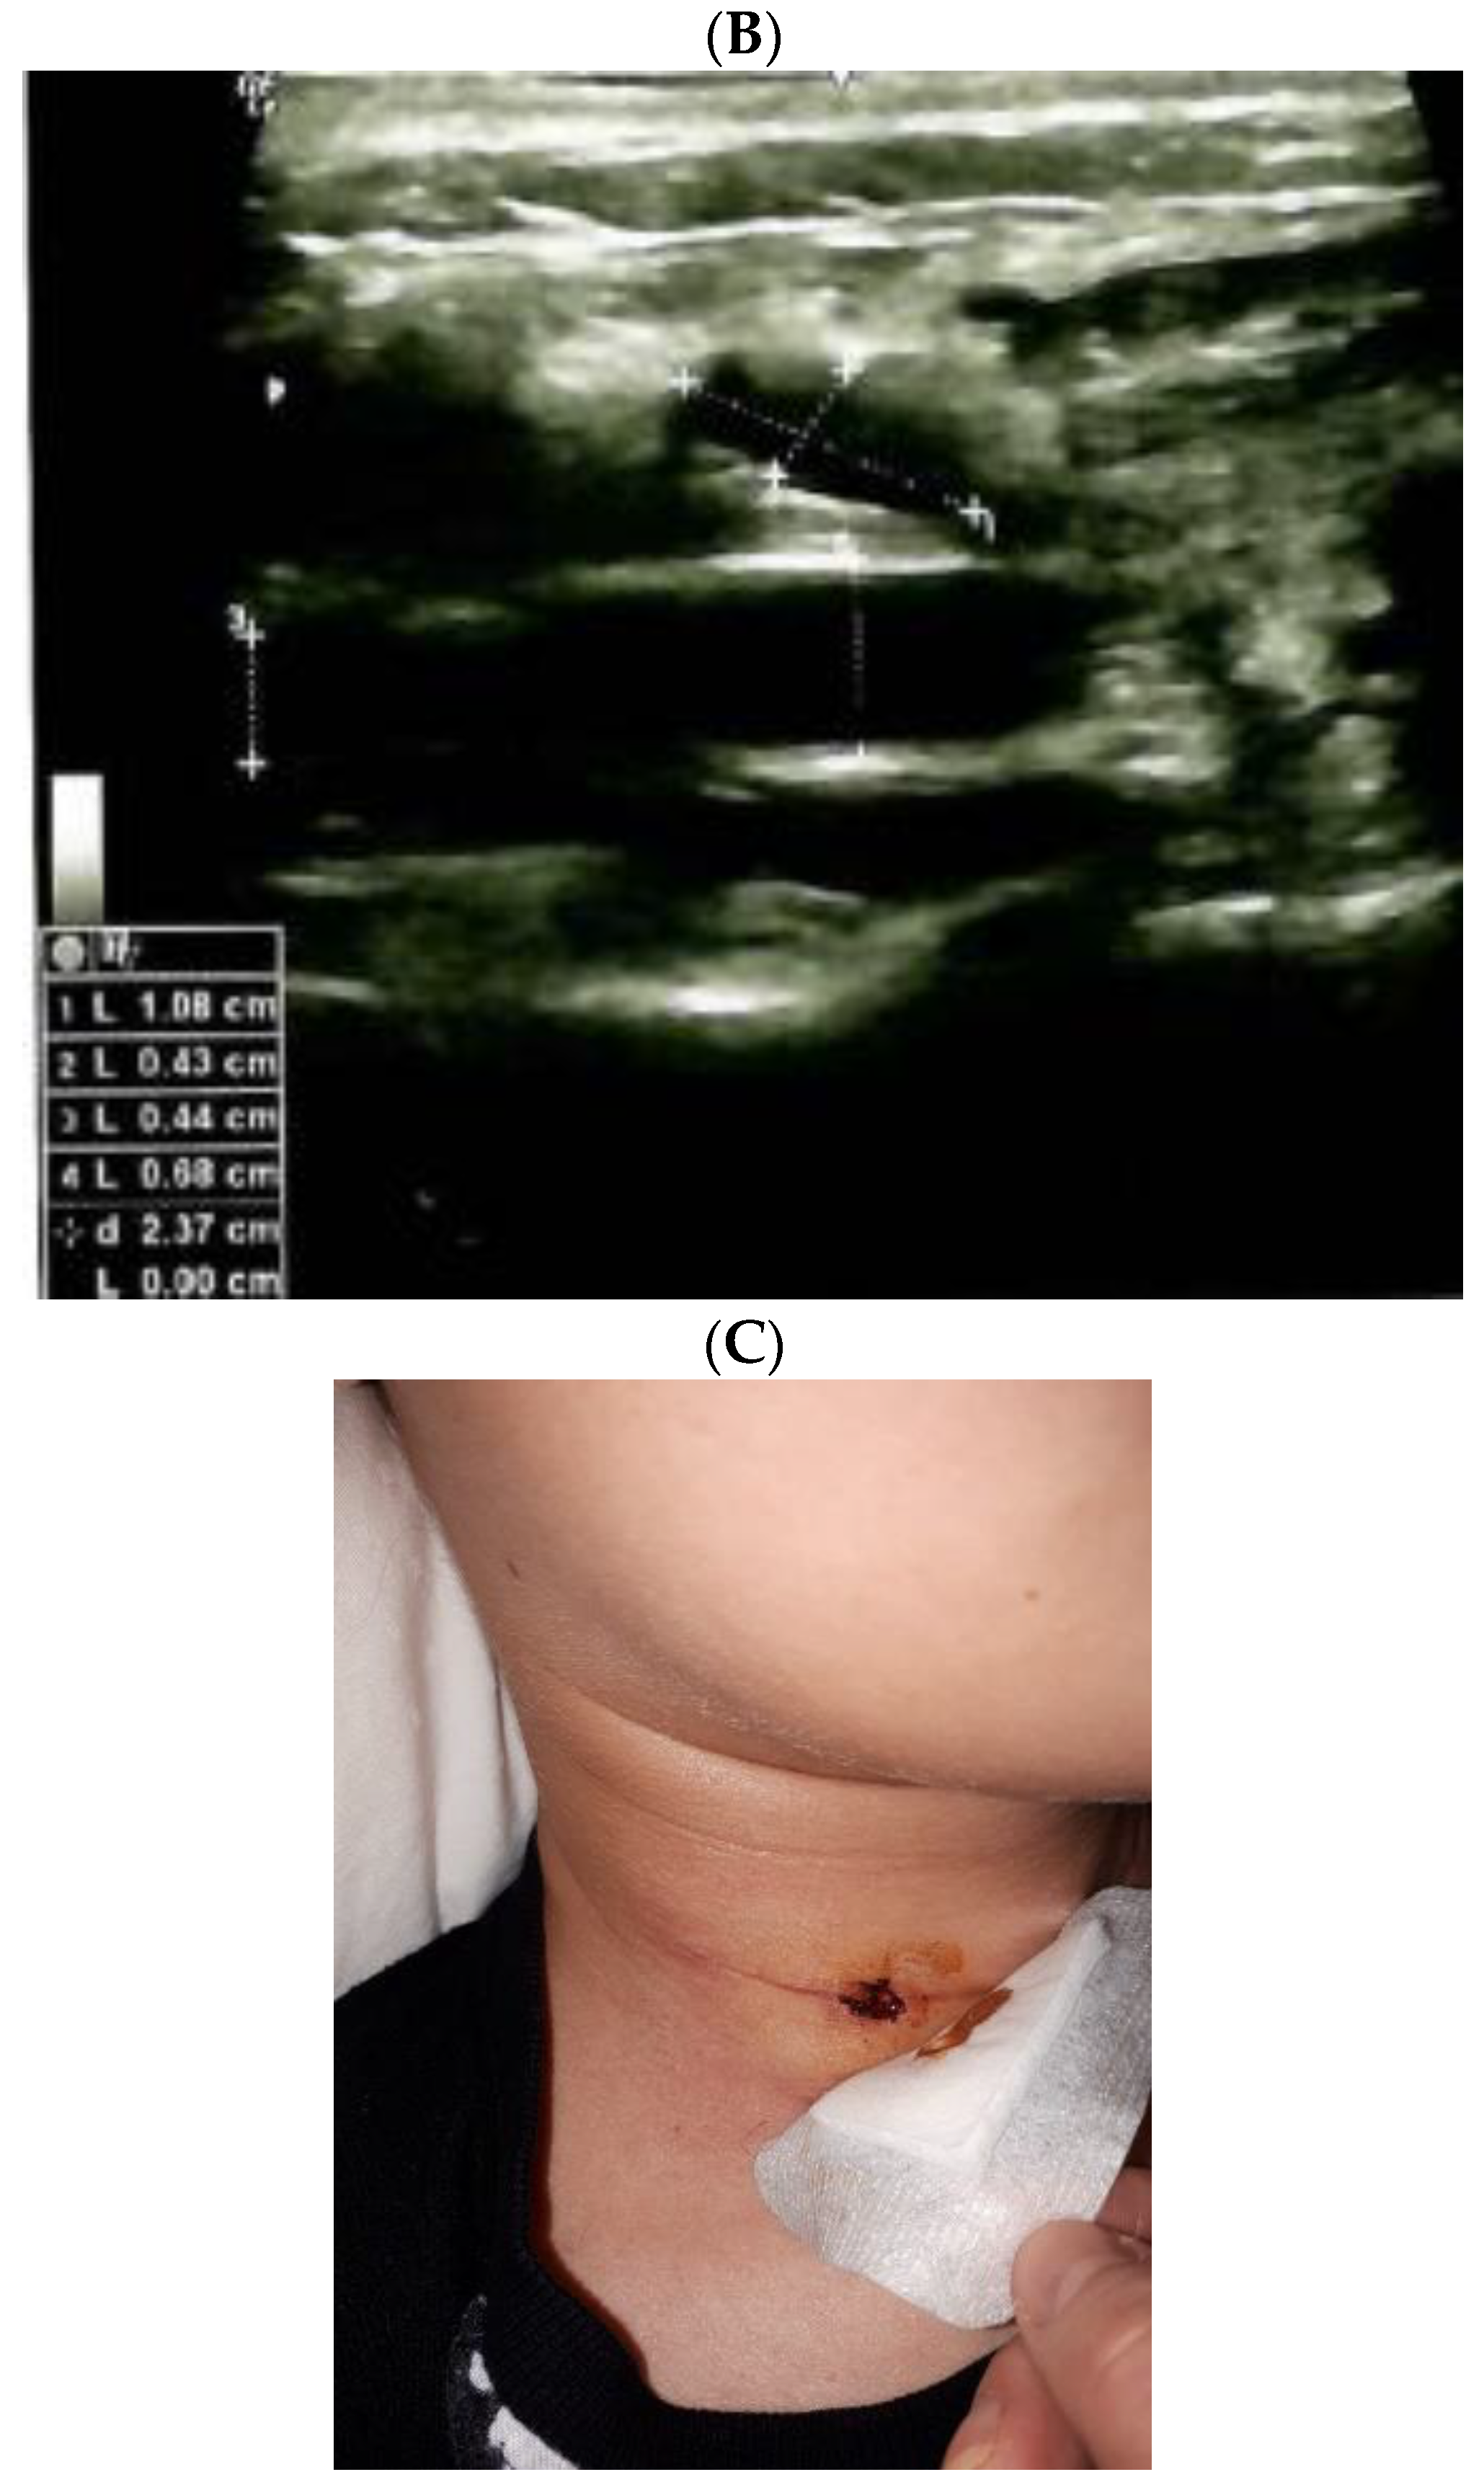

This is a 15-year-old female harboring the RET gene mutation (exon 11, pCys634Gly), consistent with familial Multiple Endocrine Neoplasia (MEN) type 2A syndrome. She was admitted 2 years ago after a total thyroidectomy with central and lateral lymph nodes dissection for a medullary thyroid cancer. Histological report confirmed a bilateral medullary microcarcinoma of 4.5/5 mm on the left lobe and of 3/3 mm on the right lobe with C-cell hyperplasia (pT1N0MO); while immunohistochemistry showed a Ki67 proliferation index of 1–2%, and positive CROMO. Post-operatory hormonal assays confirmed the normalization of pre-operatory 5-fold increase of serum calcitonin, with no other endocrine elements of MEN2A; iatrogenic post-surgery hypothyroidism was controlled under adequate daily levothyroxine substitution; she experienced transitory hypocalcemia. Second day after rapid discharge (one-day hospitalization for thyroidectomy), she first described mild droppy right eyelid followed for the next days by right eye myosis, persistent dry eye sensation, conjunctival discomfort, and episodes of alternative nasal congestion and obstruction which were actually the most disturbing clinical elements. (Figure 1).

Figure 1.

Right Horner syndrome after total thyroidectomy and lateral and central neck for medullary thyroid carcinoma.